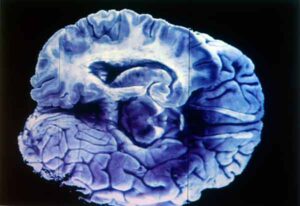

De acuerdo con el experto, la enfermedad afecta varias regiones del cerebro como el lóbulo frontal (responsable del razonamiento, conducta, planeación, parte del lenguaje, emociones, movimientos voluntarios y resolución de problemas); el temporal (cuyas funciones son la audición, el lenguaje y la memoria); y el occipital (donde ocurren la visión y la percepción visual).

La enfermedad de Alzheimer es un trastorno que empeora con el tiempo. Se caracteriza por cambios en el cerebro que derivan en depósitos de ciertas proteínas y en el desarrollo de marañas que envuelven y aíslan a las neuronas, impidiendo su conexión. “Hace que el cerebro se encoja y que las neuronas cerebrales, a la larga, mueran”, subrayó el especialista.